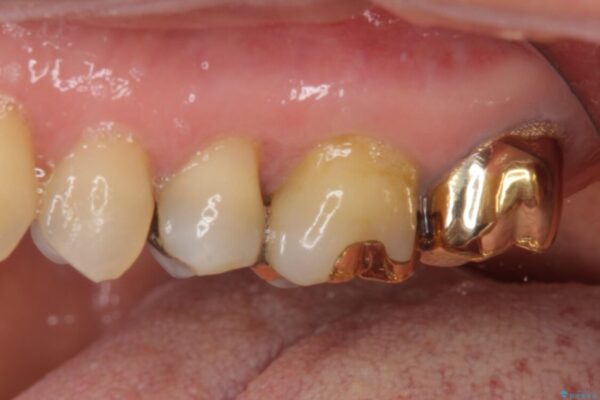

奥歯の銀歯が外れてしまったため、セラミック治療を希望された患者様です。

セラミックインレーによる修復治療を実施しました。

正面から見える場所であったため、セラミックインレーで自然な口元にすることができました。

治療前

• 外れてしまった銀歯 セラミックインレーで自然な仕上がりに 治療前画像